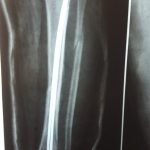

Այս ուսումնասիրությունը հիմնված է 21 հիվանդների (17 տղա, 4 աղջիկ) շարունակական խմբի բուժման արդյունքների վերլուծության վրա, որոնք ենթարկվել են տիտանե էլաստիկ մեխերով վիրահատության։ Հիվանդների տարիքը եղել է 4 տարեկանից մինչև 16 տարեկան։ 9 երեխայի մոտ կոտրվածքի պատճառ է հանդիսացել ձեռքի վրա անկումը, մնացածի մոտ կոտրվածքն առաջացել է վերջույթի ոլորման արդյունքում, վնասվածքի մեխանիզմը եղել է ուղիղ: 19 դեպքերում կոտրվածքները եղել են փակ, իսկ 2 դեպքում՝ բաց։ Ըստ վնասվածքի տեղայնացման՝ դրանք եղել են դիաֆիզար կոտրվածքներ (15 դեպք), պրոքսիմալ մետաֆիզի մակարդակի կոտրվածք (3 դեպք) և հեռավոր մետաֆիզի՝ (3 դեպք): Կոտրվածքային գծի բնույթի համաձայն՝ դիաֆիզային կոտրվածքներից հայտնաբերվել են 6 լայնակի, 4 թեք, 5 պտուտակաձև։ Մի տղայի մոտ (4 տարեկան), որի մոտ առկա էր սրունքի մ/3-ի բաց թեք կոտրվածք տեղաշարժով և մաշկի մինուս հյուսվածքներով, կատարվել է նաև վերքերի առաջնային վիրաբուժական մշակում և կարում՝ ռետինյա արտաթորիչներով։ Սակայն մի քանի շաբաթ անց սկսվել է մաշկի նեկրոզ։ Այդ իսկ կապակցությամբ կատարվել է երկրորդ վիրահատական միջամտությունը։ Կատարվել է մաշկի աուտոտրանսպլանտացիա։ Մաշկի կտորները վերցվել են առողջ ազդրի առաջային մակերեսից: (Նկ 1)

Երեխաները վիրահատված վերջույթը սկսել են օգտագործել առօրյա կյանքում (սնվել, հագնվել, հիգիենայի պարագաներ օգտագործել) օստեոսինթեզից 10-12 օր հետո։ Դպրոց հաճախելը վերսկսվել է հիվանդանոցից դուրս գրվելուց 7-10 օր հետո: Վիրահատված վերջույթի շարժման տիրույթի ամբողջական վերականգնում նկատվել է բոլոր երեխաների մոտ վիրահատական բուժումից 4-5 շաբաթ անց՝ անկախ կոտրվածքի բնույթից։ Սպորտին վերադարձը տեղի է ունեցել վիրահատությունից հետո 6 շաբաթից մինչև 3 ամիս ընկած ժամանակահատվածում՝ կախված սպորտի տեսակից և կոտրվածքի բնույթից։ Ինտրամեդուլյար մեխերի հեռացումը կատարվել է 15 դեպքերում օստեոսինթեզից 6 և ավելի ամիս անց, իսկ մնացած դեպքերում 12 ամիս անց։ Իմպլանտը հեռացվել է ընդհանուր անզգայացման տակ։ Իմպլանտի հեռացման ընթացքում կամ դրանից հետո բարդություններ չեն եղել: Բուժման ավարտից և իմպլանտների հեռացումից հետո հիվանդների արդյունքները գնահատելիս բոլոր դեպքերում գրանցվել է գերազանց արդյունք։ Հանդիպած բարդություններից եղել է 2 դեպք։ Մեկը՝ մաշկի նեկրոզ, որը պայմանավորված էր մեծ վերքի առկայությամբ կապված վնասվածքի բնույթից (ավտովրաերթ), և երկրորդը՝ ձողով մաշկի պերֆորացիա և թարախակալում։